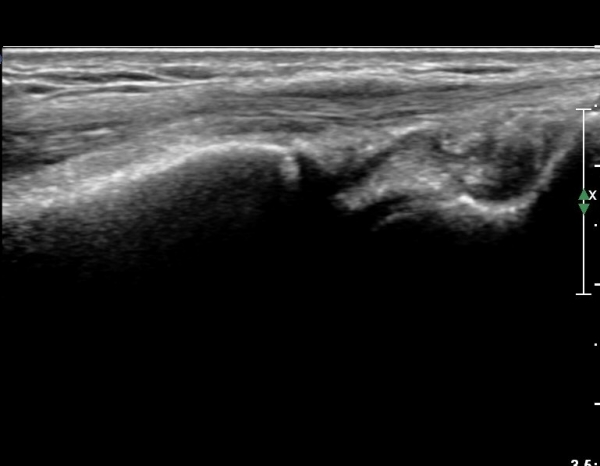

¼Õ¸ñÀÇ Á¾´Ü¸é°Ë»ç¿¡¼­ ¼Õ¸ñ °üÀý³» ºÎÁ¾ÀÌ °üÂûµÊ(»çÁø 1).

ŽÃÍÀÚ¸¦ ¾à°£ ôÃ÷À¸·Î À̵¿ÇÏ´Ï ¿ä°ñ ¸»´Ü¿¡ ÇÇÁú°ñ ¿¬°á¼º ¼Ò½Ç(loss of cotical continuity)ÀÌ °üÂûµÊ(»çÁø 2, 3).